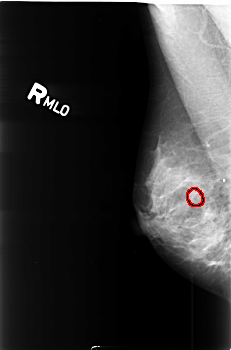

B_3419_1.RIGHT_MLO

FILE: B_3419_1.RIGHT_MLO.OVERLAY

TOTAL_ABNORMALITIES 1

ABNORMALITY 1

LESION_TYPE CALCIFICATION TYPE PLEOMORPHIC DISTRIBUTION CLUSTERED

ASSESSMENT 4

SUBTLETY 2

PATHOLOGY BENIGN

TOTAL_OUTLINES 1

BOUNDARY